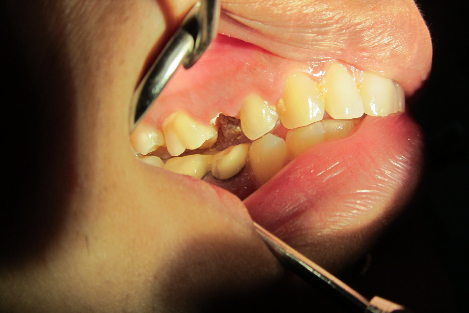

Non Vital Tooth Bleaching